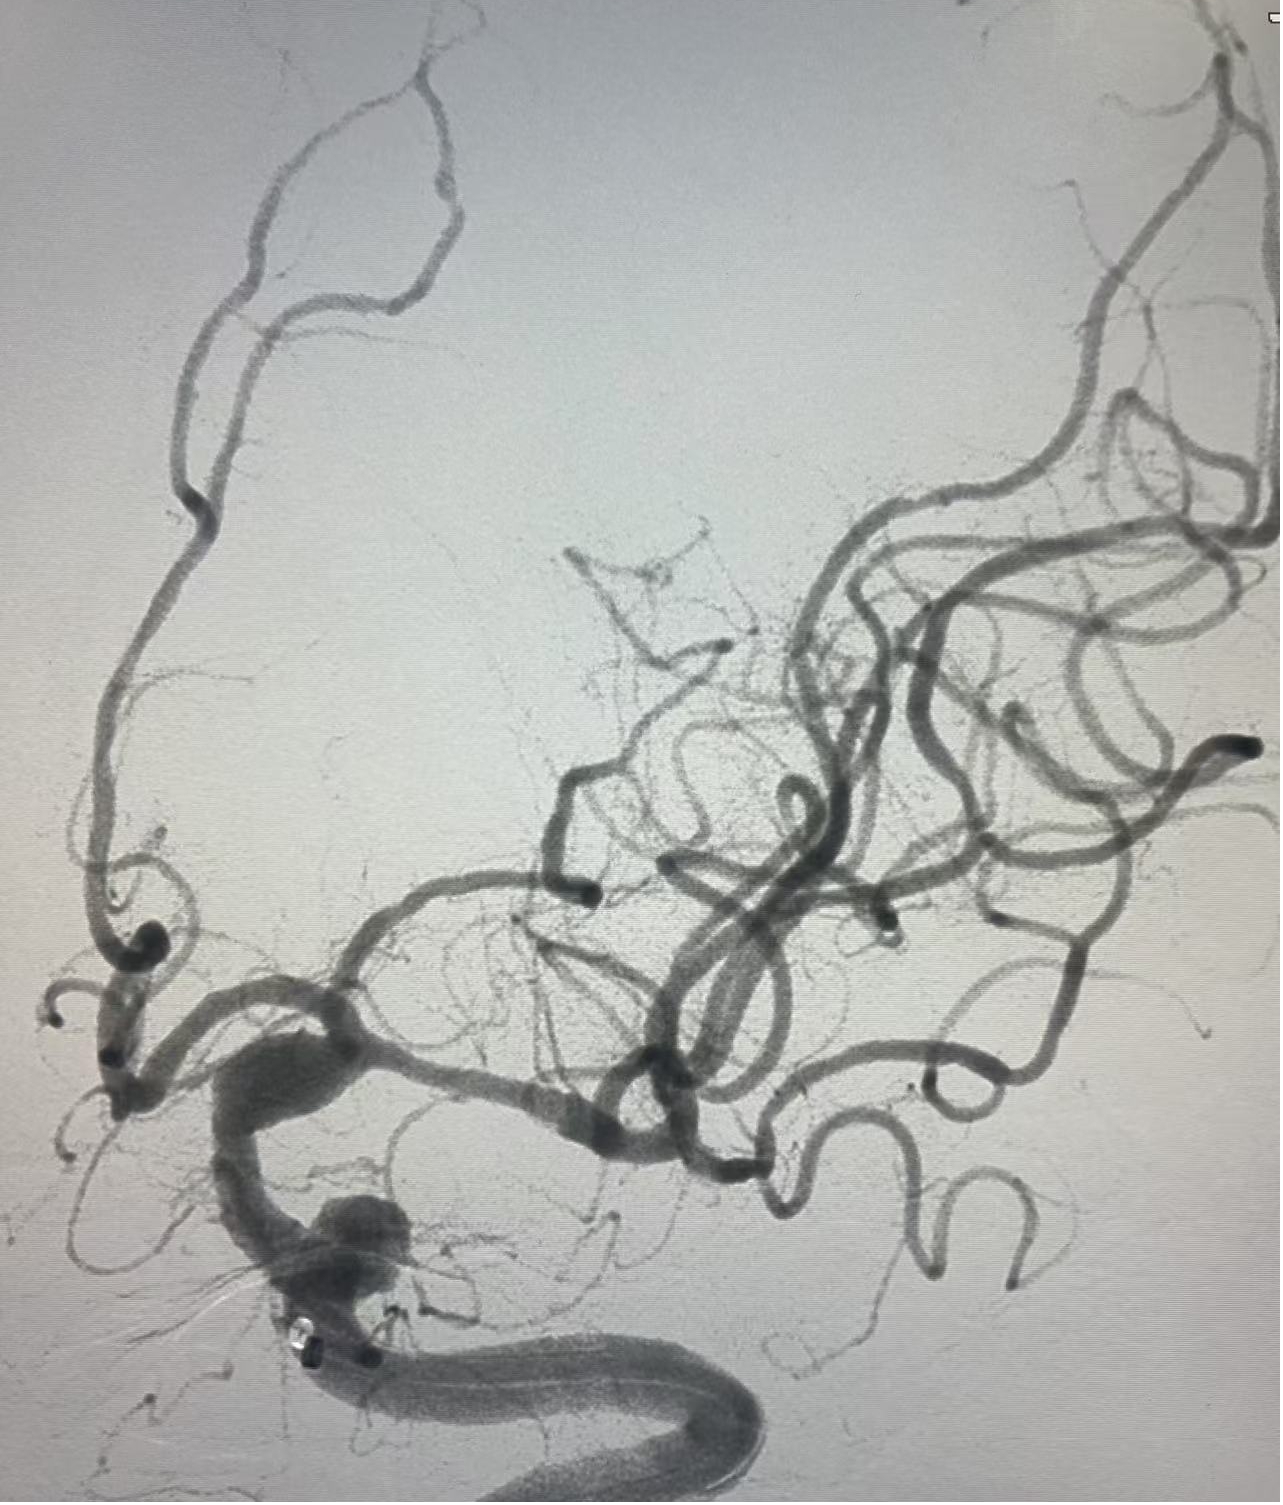

病例1:患者男,突发右侧肢体无力,伴言语不能活动4小时入急诊科,NIHSS评分:20分。入院后,立即启动卒中绿色通道,积极完成术前评估,急诊行血管内治疗,术后患者恢复良好。

手术过程

一把通畅

观察15分钟再次造影,血管通畅。